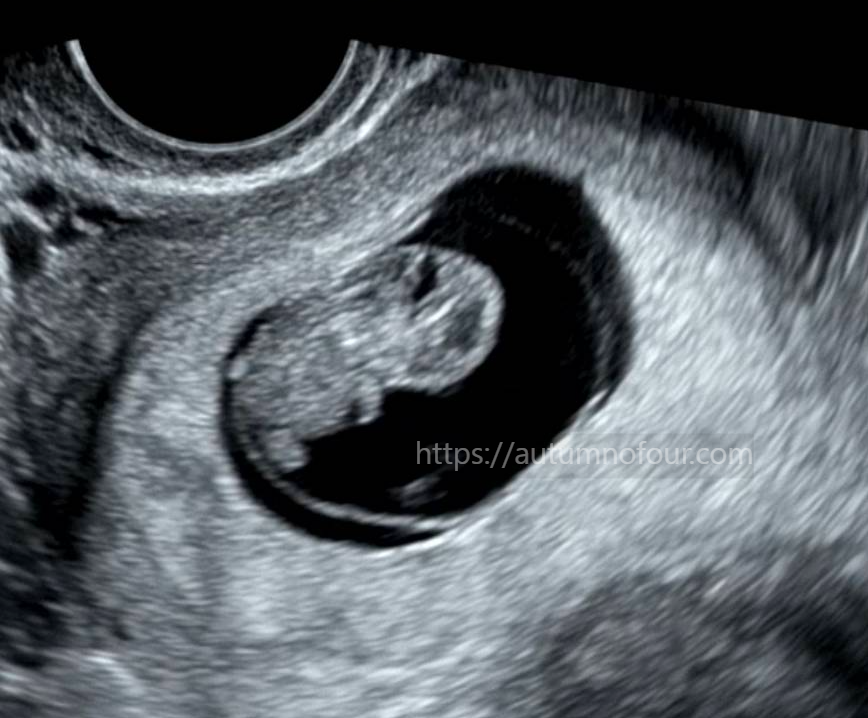

지난주와는 또 확연하게 달라진 태아의 모습!

팔과 다리가 뾱뾱 튀어나와있고

몸통과 머리도 구분이 될 정도로 성장했다.

젤리곰 같이 너무 귀엽다.

크기는 22mm가 되었고, 심장도 분당 160